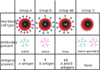

Cells

Smallest and most numerous structural unit of living matter

Connective Tissue

- –Supports and binds other body tissue and parts

- –Connective tissue consists of:

- liquid (blood)